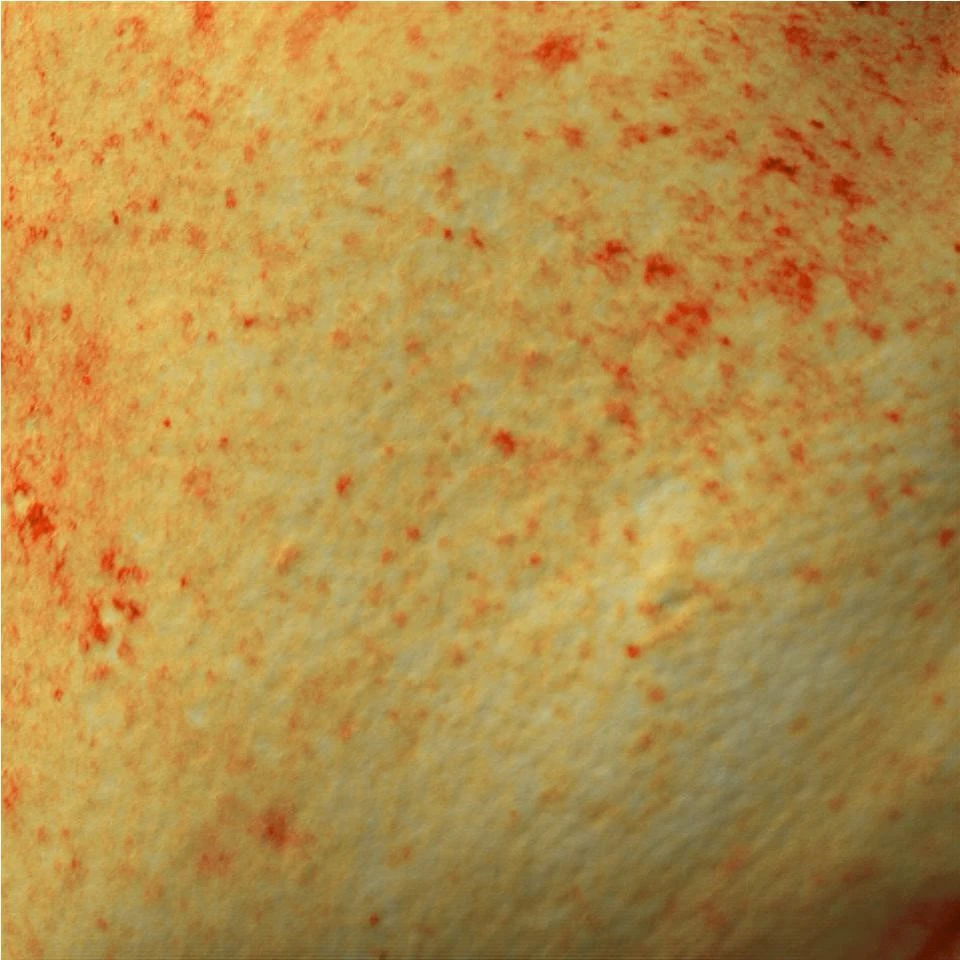

Участница 3. Пигментация кожи щеки. Фото до

до и после проведенного курса Геля PRX-T33

Участница 3. Пигментация кожи щеки. Фото после

Участница 3. Обработка фотографии в режиме «меланин». Фото до

Участница 3. Обработка фотографии в режиме «меланин». Фото после